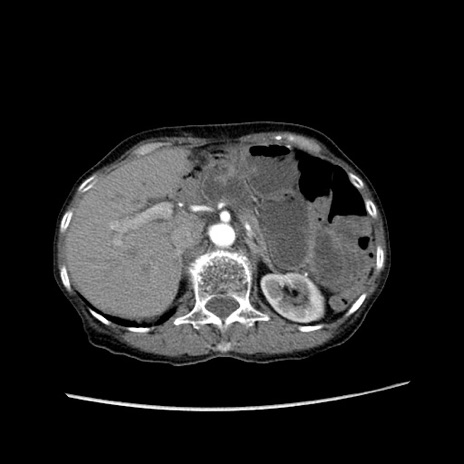

症例25(横断像)

【症例】80歳代女性

【主訴】胸のつかえ感

【現病歴】約9時間前に食後から胸のつかえた感じあり、嘔吐あり、来院。

【既往歴】胃癌(全摘)、胆摘、虫垂炎

【身体所見】心窩部に圧痛あり、反跳痛なし。

【データ】WBC 5700、CRP 0.05